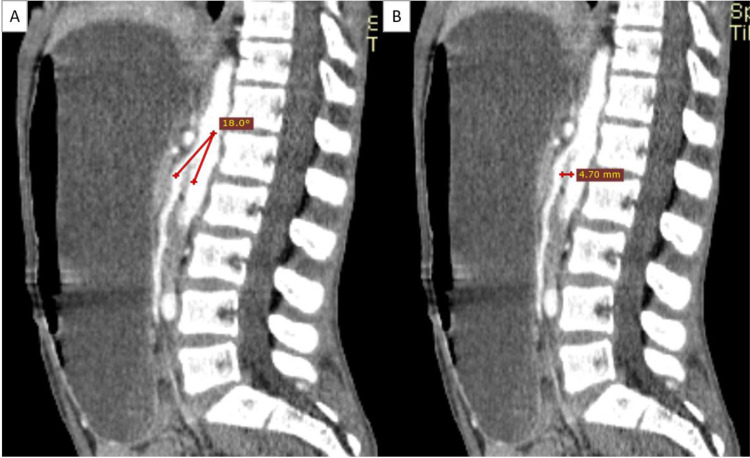

Superior mesenteric artery (SMA) syndrome, also known as Wilkie syndrome, is an uncommon condition marked by the compression of the third segment of the duodenum between the SMA and the aorta, often occurring after rapid weight loss, particularly in young, slim individuals. Symptoms consist of epigastric pain, bloating, and vomiting. Nutcracker syndrome (NCS) is characterized by the compression of the left renal vein (LRV) between the superior mesenteric artery and the aorta. This condition results in venous varices and elevated pressure within the LRV, which may manifest as hematuria, proteinuria, pelvic congestion, and flank pain. Although each of these syndromes is infrequent, their simultaneous incidence is remarkably occasional. This case report examines a young male patient diagnosed with both SMA syndrome and NCS, emphasizing the importance of considering these conditions in the differential diagnosis of abdominal and renal symptoms.